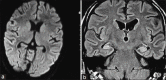

Results: There were 15 (males = 10) patients of autoimmune encephalitis. The mean age of presentation was 24 years (range: 2-64 years). The most common onset was subacute (64%) and four (29%) patients presented as SE. Predominant clinical presentations were seizures (100%) almost of every semiology. CSF was done in 10 patients; it was normal in 60%. Brain MRI was done in all patients, in six (40%) it was normal, six (40%) showed T2W and FLAIR hyperintensities in bilateral limbic areas. Antibodies found were the N-methyl-D-aspartate receptor antibody in seven (50%), voltage-gated potassium channel antibody in five (36%), two of antiglutamic acid decarboxylase, and one patient with double stranded DNA (dsDNA) antibodies. None showed evidence of malignancy. Patients received immunotherapy, either steroids, intravenous immunoglobulin, or both. Follow-up showed significant improvement in majority of cases, neither further seizures nor relapse in nine (67%) cases. One death occurred, due to delayed presentation.